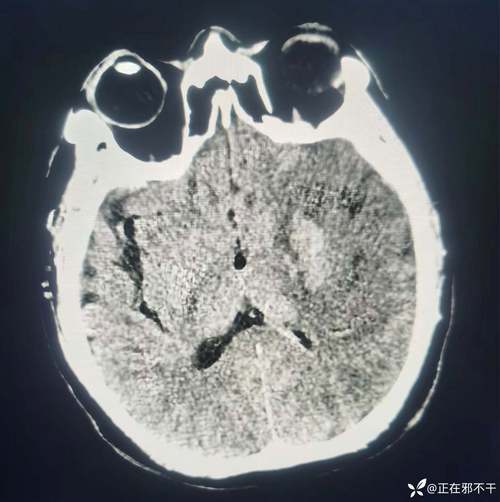

| 影像学检查 | CT:高密度影,能立刻看到血肿 | CT:早期可能正常,24-48小时后出现低密度影 MRI (磁共振):能更早发现缺血灶 |